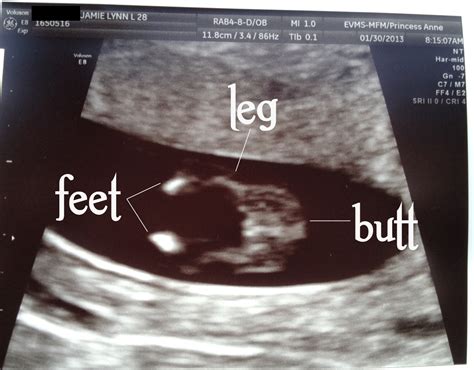

• Visualizing the Baby: At 12 weeks, the baby is about the size of a plum and has distinct features, including a head, body, and limbs. The ultrasound will show the baby’s movements, such as sucking its thumb or curling its toes.

• Nuchal Translucency Measurement: The technician will measure the thickness of the nuchal translucency, which is an important indicator of the baby’s health. This measurement, along with other factors, helps assess the risk of chromosomal abnormalities like Down syndrome.